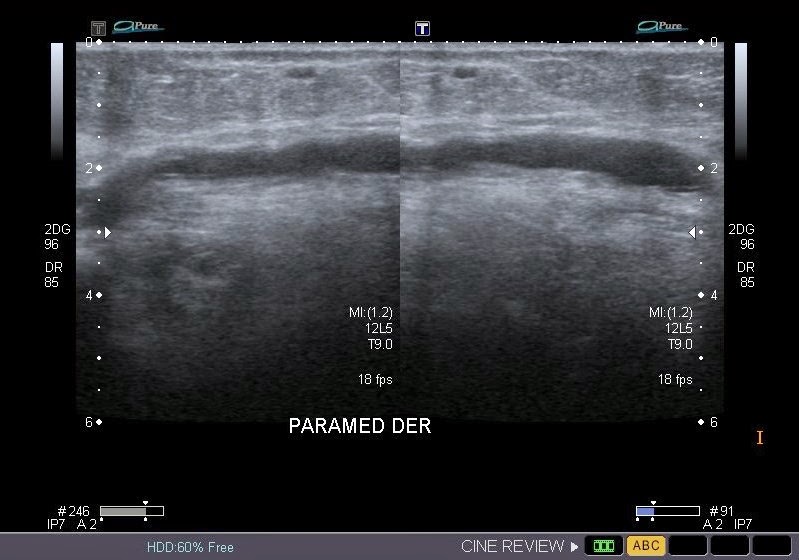

INGRESO

Paciente con antecedente de ALIF (Fusión lumbar intersomática anterior) 360 grados L5-S1 hace siete meses, quién presenta herida de abordaje anterior con dehiscencia de sutura, con cierre por segunda intención, quien consulta por cuadro clínico de dos días de secreción purulenta en herida quirúrgica, niega fiebre, niega otras sintomatología, refiere episodios previos similares.

EVOLUCIÓN

Paciente en POP de ALIF L5-S1 quien presento dehiscencia de la herida abdominal con ISO superficial ya tratada, sin embargo persiste con dehiscencia y desde ayer con supuración asociado a fiebre subjetiva. Se realiza eco abdominal con colección en pared sugestiva de absceso, elevación de RFA por lo cual se considera se debe hospitalizar para manejo antibiótico, drenaje de la colección, manejo médico y vigilancia neurológica.